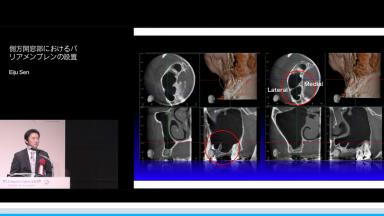

側方開窓部におけるバリアメンブレンの設置

本講演では,上顎洞底挙上術の一手法である側方開窓術の術前臨床的判断基準,術式詳細,臨床経過,CBCT所見,術後偶発症,文献的考察から,開窓部へのバリアメンブレン設置を整理する.